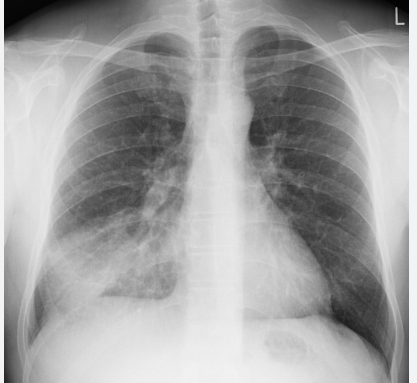

This CXR causes hypoxia due to which underlying mechanism

Pneumothorax causing V/Q mismatch